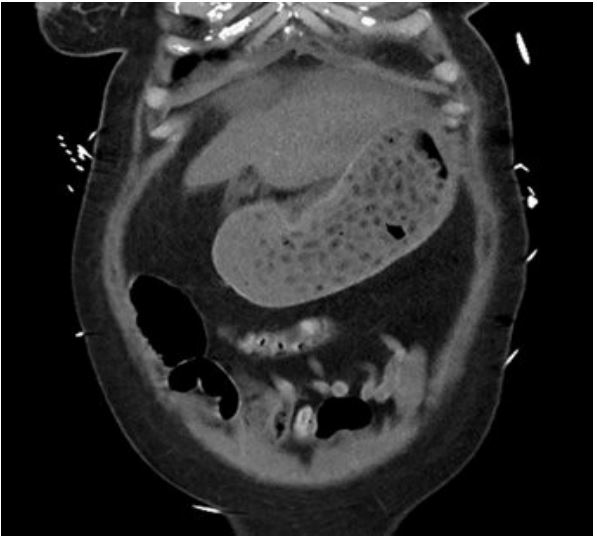

NGT was inserted, aspirating red-colored fluid with pill fragments. Activated charcoal was then administered and urgent abdominal CT scan organized. This revealed a moderate volume of variable attenuation gastric content in the stomach without further characterization (Figure 3).

Delayed gastric emptying and pharmacobezoar formation set the stage for endoscopic intervention as possibly the most appropriate method of decontamination. Timely imaging such as CT scan can be invaluable in confirming pharmacobezoar. However, case 2 shows that the presence of pills versus food may not be radiologically distinguishable. Gastroscopy may still be indicated in such cases and indeed be a lifesaving intervention. Nevertheless, we believe that timely cross-sectional imaging (i.e., upon arrival to ED) should guide the indication to urgent gastroscopy, as absence of significant gastric content may render gastroscopy unnecessary.